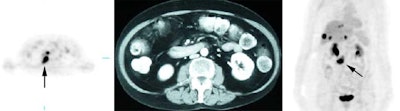

Monitor response to therapy in lymphoma: The patient shown below had a history of Hodgkins lymphoma and had undergone stem cell transplant. A follow-up CT scan revealed increased soft tissue in the region of the porta hepatis which was suspicious for adenopathy, but the patient's lack of internal fat limited the CT evaluation. The patients FDG PET exam revealed widespread intra-abdominal, pelvic, and inguinal adenopathy consistent with extensive recurrent lymphoma which was not appreciated on the CT exam. Case courtesy of CTI PET Systems, Inc. |

|